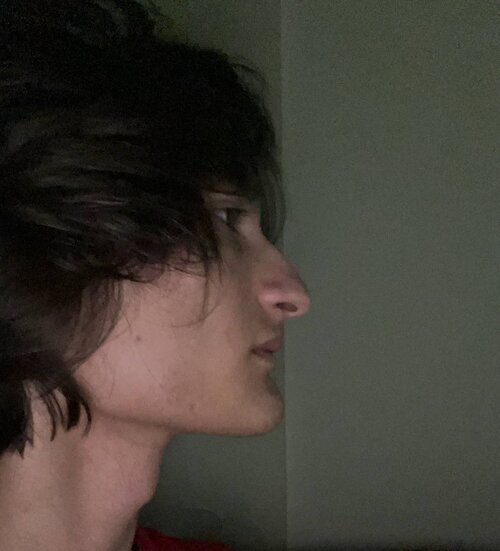

Rhino ik, Here's a photo:

Rhino ik, Here's a photo: